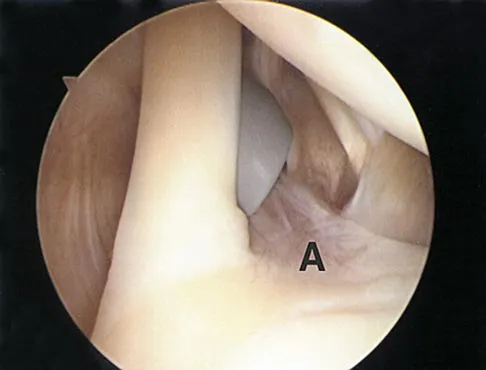

In the arthroscopic photograph shown in Figure 5, the structure labeled "A" functions primarily as a restraint to translation of the humeral head in what direction?

Explanation